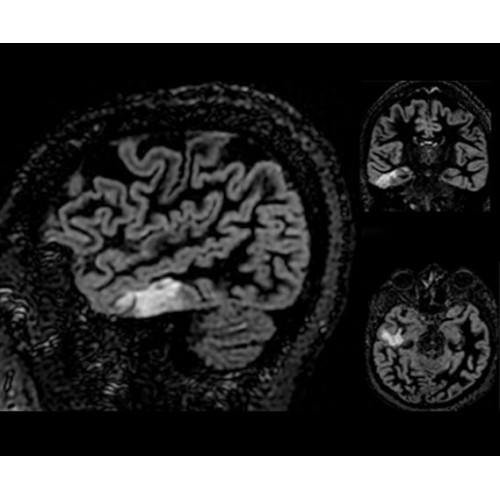

SIGNA PET/MR 3.0T — это гибридная система, в которой совмещаются две принципиально разные технологии — магнитно-резонансную томографию (МРТ) и позитронно-эмиссионную томографию (ПЭТ). Система отличающийся высокой чувствительностью и эффективностью и предназначена для диагностики в области онкологии, неврологии, кардио-васкулярных исследований, исследований воспалительных процессов.

Компания GE Healthcare представляет революционную, полностью интегрированную систему SIGNA PET/MR1, в которой сочетаются времяпролетная технология (TOF) и возможности напряженности магнитного поля 3.0 Тл. Мы поможем вам поднять исследования на более высокий уровень. SIGNA PET/MR позволяет достичь впечатляющей точности и скорости исследований, а благодаря новейшей технологии реконструкции Q.Clear2 качество изображений улучшается в два раза. Кроме того, в систему включен полный набор клинических приложений и гибких катушек для проведения любых видов исследования, открывая для вас возможности визуализации, о которых вы даже не догадывались.

Кроме того, в результате использования технологии TOF и инновационной технологии реконструкции Q.Clear вы сможете добиться прекрасного соотношения сигнал/шум. А благодаря технологии нулевого времени эхо (ZTE) визуализировать костную структуру без ионизирующего излучения. Все эти разработки для улучшения качества сканирования и точности анализа помогут вам использовать весь потенциал ПЭТ/МРТ.

• МРТ с функцией нулевого времени эхо (ZTE) отличается точностью, возможностью персональных настроек и отсутствием ионизирующего излучения. Она приходит на смену традиционному исследованию на основе рентгеновского излучения. МРТ с функцией нулевого времени эхо (ZTE) на базе SIGNA ПЭТ/МРТ является более надежной и быстрой по сравнению с системами, использующими сверхмалое время эхо (UTE).

• Специальный пакет приложений для измерения и сравнения объемных изображений ЦНС с нормами поможет вам в диагностике нейродегенеративных заболеваний, а дополнительные инструменты визуализации — в постановке точного диагноза с помощью бета-амилоидов и радиоизотопных маркеров ФДГ.